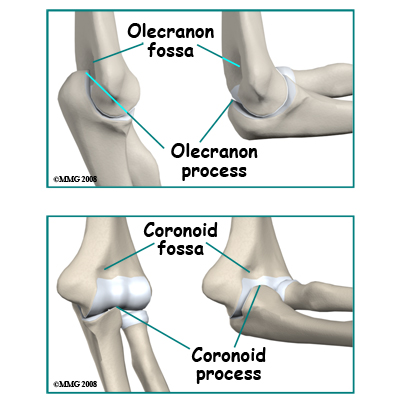

There are three features of articular cartilage that are important when considering fractures that involve a joint. First, articular cartilage is nourished by joint fluid and does not have a blood supply of its own. Secondly, articular cartilage does not re-grow. Any damage to articular cartilage is permanent. Any gaps or ridges in a joint will be filled in with scar tissue rather than articular cartilage. Thirdly, blood vessels do not penetrate through the joint surface. All the blood supply of the bone that supports articular cartilage comes from inside the bone rather than from the side covered with articular cartilage. If a fracture breaks off a piece of bone that is covered by articular cartilage, the bone loses its blood supply and will die. The articular cartilage remains viable because it is still bathed in joint fluid. Some elbow fractures do result in multiple fragments of the joint surface. On a positive note, if the fragments remain in good position the joint surface will survive and the bone may grow underneath the surface to support it. The upper end of the ulna (the bone on the inside of your arm) is shaped like a hook. When the elbow is straight the olecranon process (the tip of the hook) fits into a cavity in the back of the humerus (the olecranon fossa). When the elbow is fully bent the prominence on the front of the ulna (the coronoid process) fits into a cavity in the front of the humerus (the coronoid fossa). The joint surface of the ulna is shaped like the roof of a house and fits into a corresponding groove in the surface of the humerus (the troclear groove). This gives some side-to-side stability to the joint.

The upper end of the ulna (the bone on the inside of your arm) is shaped like a hook. When the elbow is straight the olecranon process (the tip of the hook) fits into a cavity in the back of the humerus (the olecranon fossa). When the elbow is fully bent the prominence on the front of the ulna (the coronoid process) fits into a cavity in the front of the humerus (the coronoid fossa). The joint surface of the ulna is shaped like the roof of a house and fits into a corresponding groove in the surface of the humerus (the troclear groove). This gives some side-to-side stability to the joint.